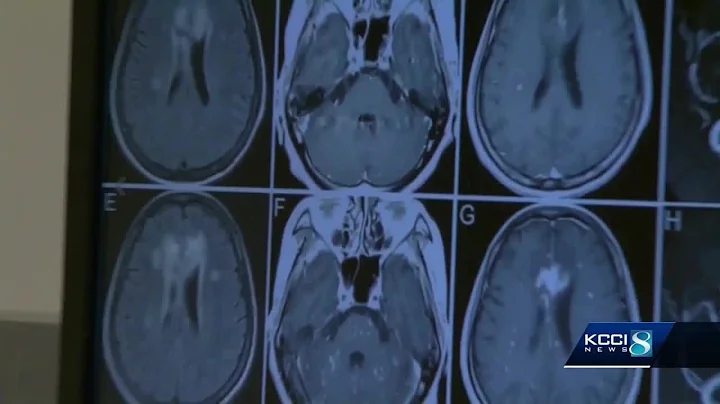

Blood Test Could Detect Alzheimer's Up To 16 Years Before Symptoms Begin, Study Says

A simple blood test could predict if a patient will develop Alzheimer's disease up to 16 years before symptoms begin, a new study ...